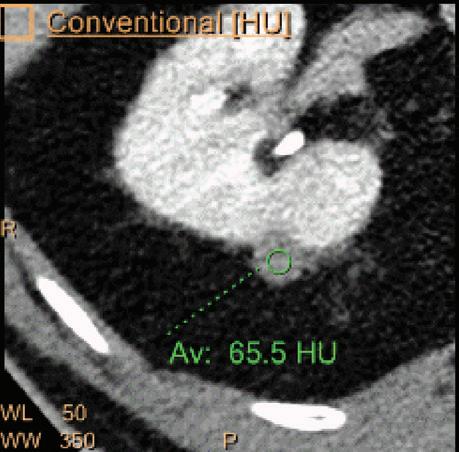

A hyperdense lesion (65 HU) is visible on the right kidney on the conventional CT images obtained after contrast enhancement. The TNC image is shown in the upper right corner. The lower row displays spectral results in the Magic Glass, from left to right: conventional CT image, VNC image, Iodine no Water image, and iodine density image. Comparison between measurements performed on the TNC (55.4 HU) and VNC images (57.6 HU) demonstrates only a minor difference between them (difference = 2.2 HU), showing that the VNC images could perfectly replace the TNC images in this clinical scenario. Iodine concentration measurements in the same region of interest show values of no more than 0.3 mg/ml which can be considered as negligible. In other words, there is no contrast medium uptake in the lesion which can thus be considered as benign. The hyperdensity is of a hemorrhagic cyst.